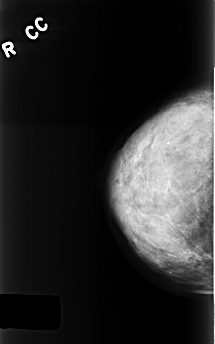

C_0400_1.RIGHT_CC

RIGHT_CC LINES 4464 PIXELS_PER_LINE 2784 BITS_PER_PIXEL 12 RESOLUTION 50 NON_OVERLAY